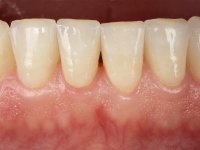

Paciente do sexo masculino, com 36 anos, não fumador. Fez tratamento ortodôntico e reabilitou esteticamente o sector anterior com restaurações em resina composta. As restaurações apresentavam um aumento vertical médio de 2 mm em relação o bordo incisal. Apresentavam-se esteticamente satisfatórias, mas com algumas fraturas incisais. O dente 1.5 apresentava um processo apical e o dente 2.6 apresentava tratamento endodôntico e uma lesão endo-periodontal. No maxilar inferior no local do dente 3.5 apresentava um implante com uma coroa aparafusada e o dente 8.5 ainda estava presente em boca com agenesia do dente 4.5. O paciente apresentava uma ligeira perda da dimensão vertical da oclusão provavelmente associada a um visível desgaste das superfícies oclusais. O periodonto era espesso e apresentava uma excelente higiene oral.

Realizado o diagnóstico e tomada a decisão quanto ao tratamento a executar, tornou-se importante definir qual a sequência de trabalho a adotar no sentido de conseguir a reabilitação da D.V.O. (V.D.O), de forma progressiva e equilibrada. Na primeira fase fez-se uma pré-impressão da arcada inferior com silicone tipo “putty” e em seguida realizou-se o preparo dentário de todo o sector posterior. O preparo para os overlays foi feito coronalmente à linha amelo cementaria no sentido de ser o mais conservador possível. A impressão foi feita com técnica de dupla mistura após afastamento gengival realizado com pasta de caulino. A provisória foi realizada com resina composta de polimerização dual. Em laboratório foram realizados os overlays após se ter aberto ligeiramente (1,5mm) a D.V.O. nos modelos montados em articulador semi-ajustável. Simultaneamente o sector antero-inferior foi encerado no sentido de acompanhar este aumento da D.V.O. Também foi confecionada uma chave de silicone translucido para posterior confeção dos provisórios antero-inferiores. Em boca foi primeiro realizada a provisionalização dos dentes anteriores utilizando resina composta previamente aquecida após preparação das superfícies dentárias para a adesão. Foi colocado o dique de borracha para promover o isolamento absoluto e posteriormente foram colados os overlays. Em laboratório foi realizada nova chave de silicone para confecionar os provisórios antero-superiores. Seguidamente em boca foram preparados os seis dentes antero-superiores após colocação do fio de afastamento gengival. Feita a preparação adequada das superfícies dentárias foi realizada a impressão com técnica de dupla mistura e a respetiva provisória. Em laboratório foram confecionadas 6 facetas feldespáticas num modelo de trabalho tipo “Geller”. A provisória foi removida e as facetas foram coladas em boca utilizando um isolamento relativo competente. Esta opção foi tomada em virtude de uma prévia experiencia negativa com a colocação do dique de borracha na mandibula. Após a colagem dos laminados antero-superiores foram dadas 12 semanas para avaliar a adaptação do paciente à nova situação e então iniciar a confeção das facetas antero-inferiores. Após colocação do fio de afastamento gengival. foram feitos os preparos dentários adequados e em seguida foi feita a impressão. Também foi feita a preparação do dente 3.4 que, entretanto, tinha sofrido uma fratura do overlay. As facetas e a restauração do 3.4 foram realizadas num modelo de trabalho tipo “Geller”. Após remoção da provisória, as facetas foram coladas em boca, utilizando um isolamento relativo pelas razões apontadas anteriormente. Após colocação do trabalho o paciente foi reabilitado por outros colegas com um implante na zona do 2.6 e substituição da coroa aparafusada sobre o implante colocado no local do 3.5. Posteriormente surgiram fraturas nos overlays dos dentes 4.7 e 3.7 que foram reabilitados com overlays em Zr.